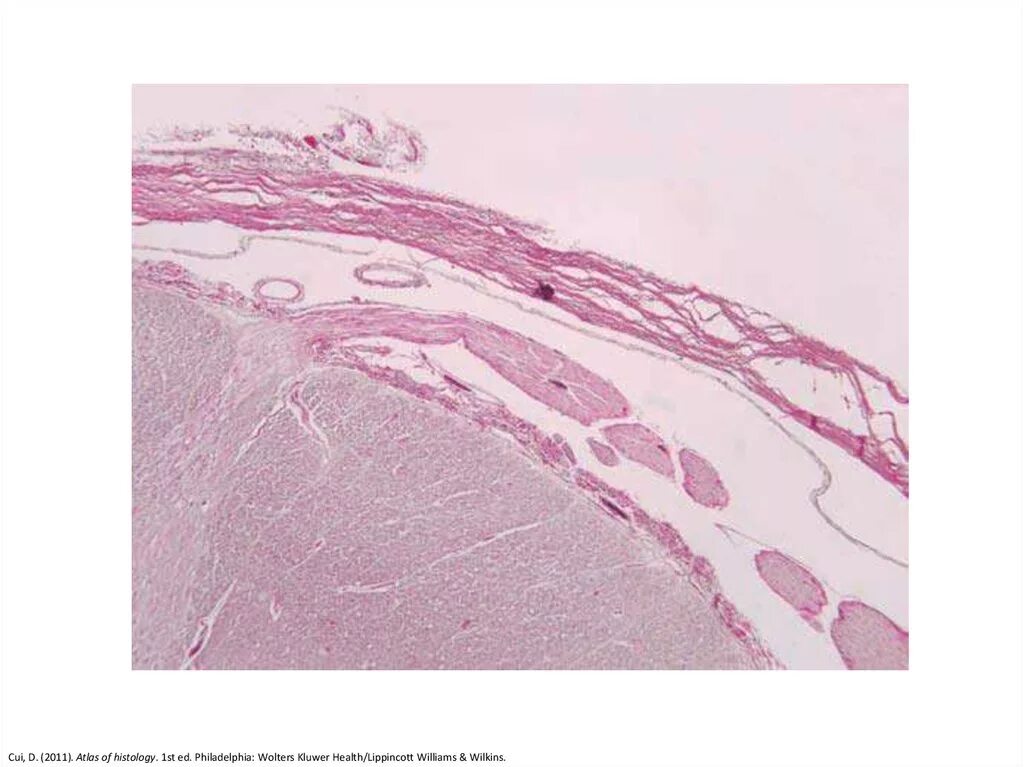

Гистология головного мозга